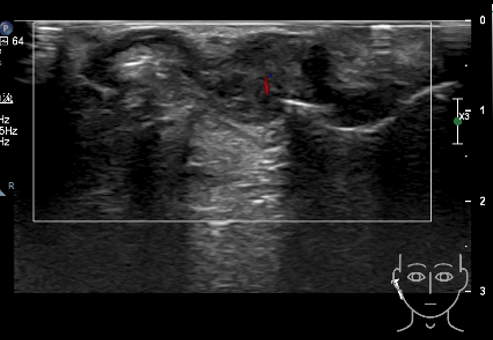

右耳软骨前后部见一低回声团,范围 3.9cm×1.9cm ,边界欠清,形态不规则,内回声不均,可见少许血流信号(见图 2-3 )。

图 2 肿物二维声像图

图 3 肿物彩色多普勒图 肿物内可见少许血流信号